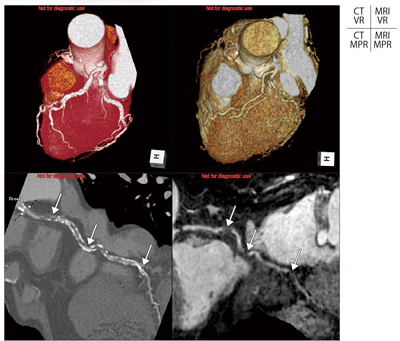

図3 症例1:外科手術前の 冠動脈スクリーニングの必要性

この症例では,術前冠動脈CT検査で,LAD#7に有意狭窄を認め,RCA#2にCTOを認めた。心疾患のリスクファクターが高く,心電図異常が指摘された患者様には冠動脈スクリーニングが有効である。術者は心疾患の合併に恐れることなく,外科手術に集中できる環境を自ら作ることが可能となる。

63歳,男性。人工透析を行っている患者様で,冠動脈の高度石灰化症例である。石灰化スコアは11294で,3枝すべてに高度石灰化(3枝ともに>2000)を認め,CT画像上では狭窄の評価は困難であった。そこで,患者様の同意を得て,直ちに冠動脈MRA検査を施行した。冠動脈MRA検査の結果,LADおよびLCXには明らかな狭窄病変を認めず,RCAの#2および#3の高度石灰化のために評価困難であった部位は,冠動脈MRAの所見と合わせて評価することで,有意狭窄であることが判断できた(図4)。われわれは,この症例を経験して以後,腎不全症例に対して患者様の希望があればCTによる造影検査は施行せず,単純CTによる石灰化スコアの評価を実施後に非造影冠動脈MRA検査を施行するようにしている(図5)。MRIはその原理的な特徴により,石灰化からのMR信号を得ることができない。冠動脈MRA検査は,このような高度石灰化症例でも,狭窄内腔の描出が妨げられないため絶好の検査方法となる1)。

図4 症例2:冠動脈高度石灰化の冠動脈CTAと冠動脈MRA

CTでは高度石灰化のために詳細評価が困難であるが,MRAと組み合わせることで責任病変を同定することが可能となる。このようなアプローチができれば,石灰化病変に悩む透析患者の冠動脈スクリーニングがもっと身近なものとなることが期待される。